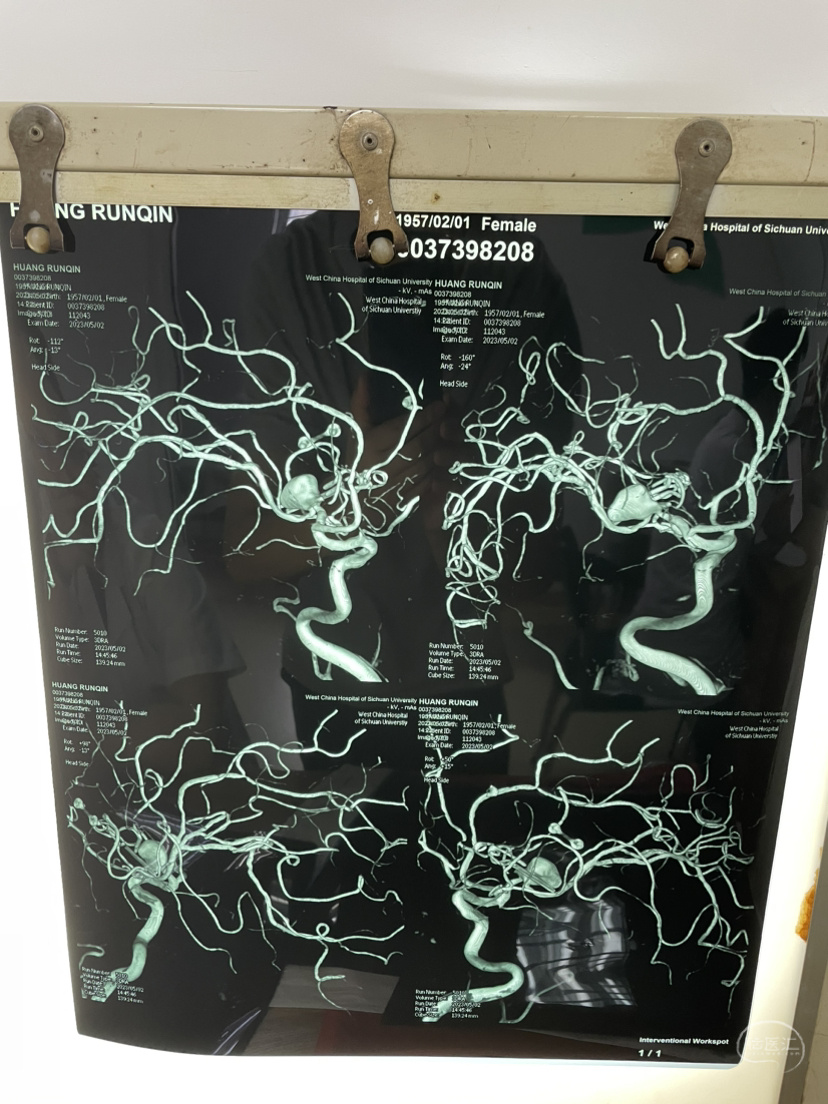

夹闭术后两个月,出院后一个月!再次出血,血肿量大,患者清醒!转上级市级医院,拟予介入栓塞后清除血肿

家属选择保守治疗,患者一直清醒!两个月前在华西行介入栓塞术,血肿吸收!